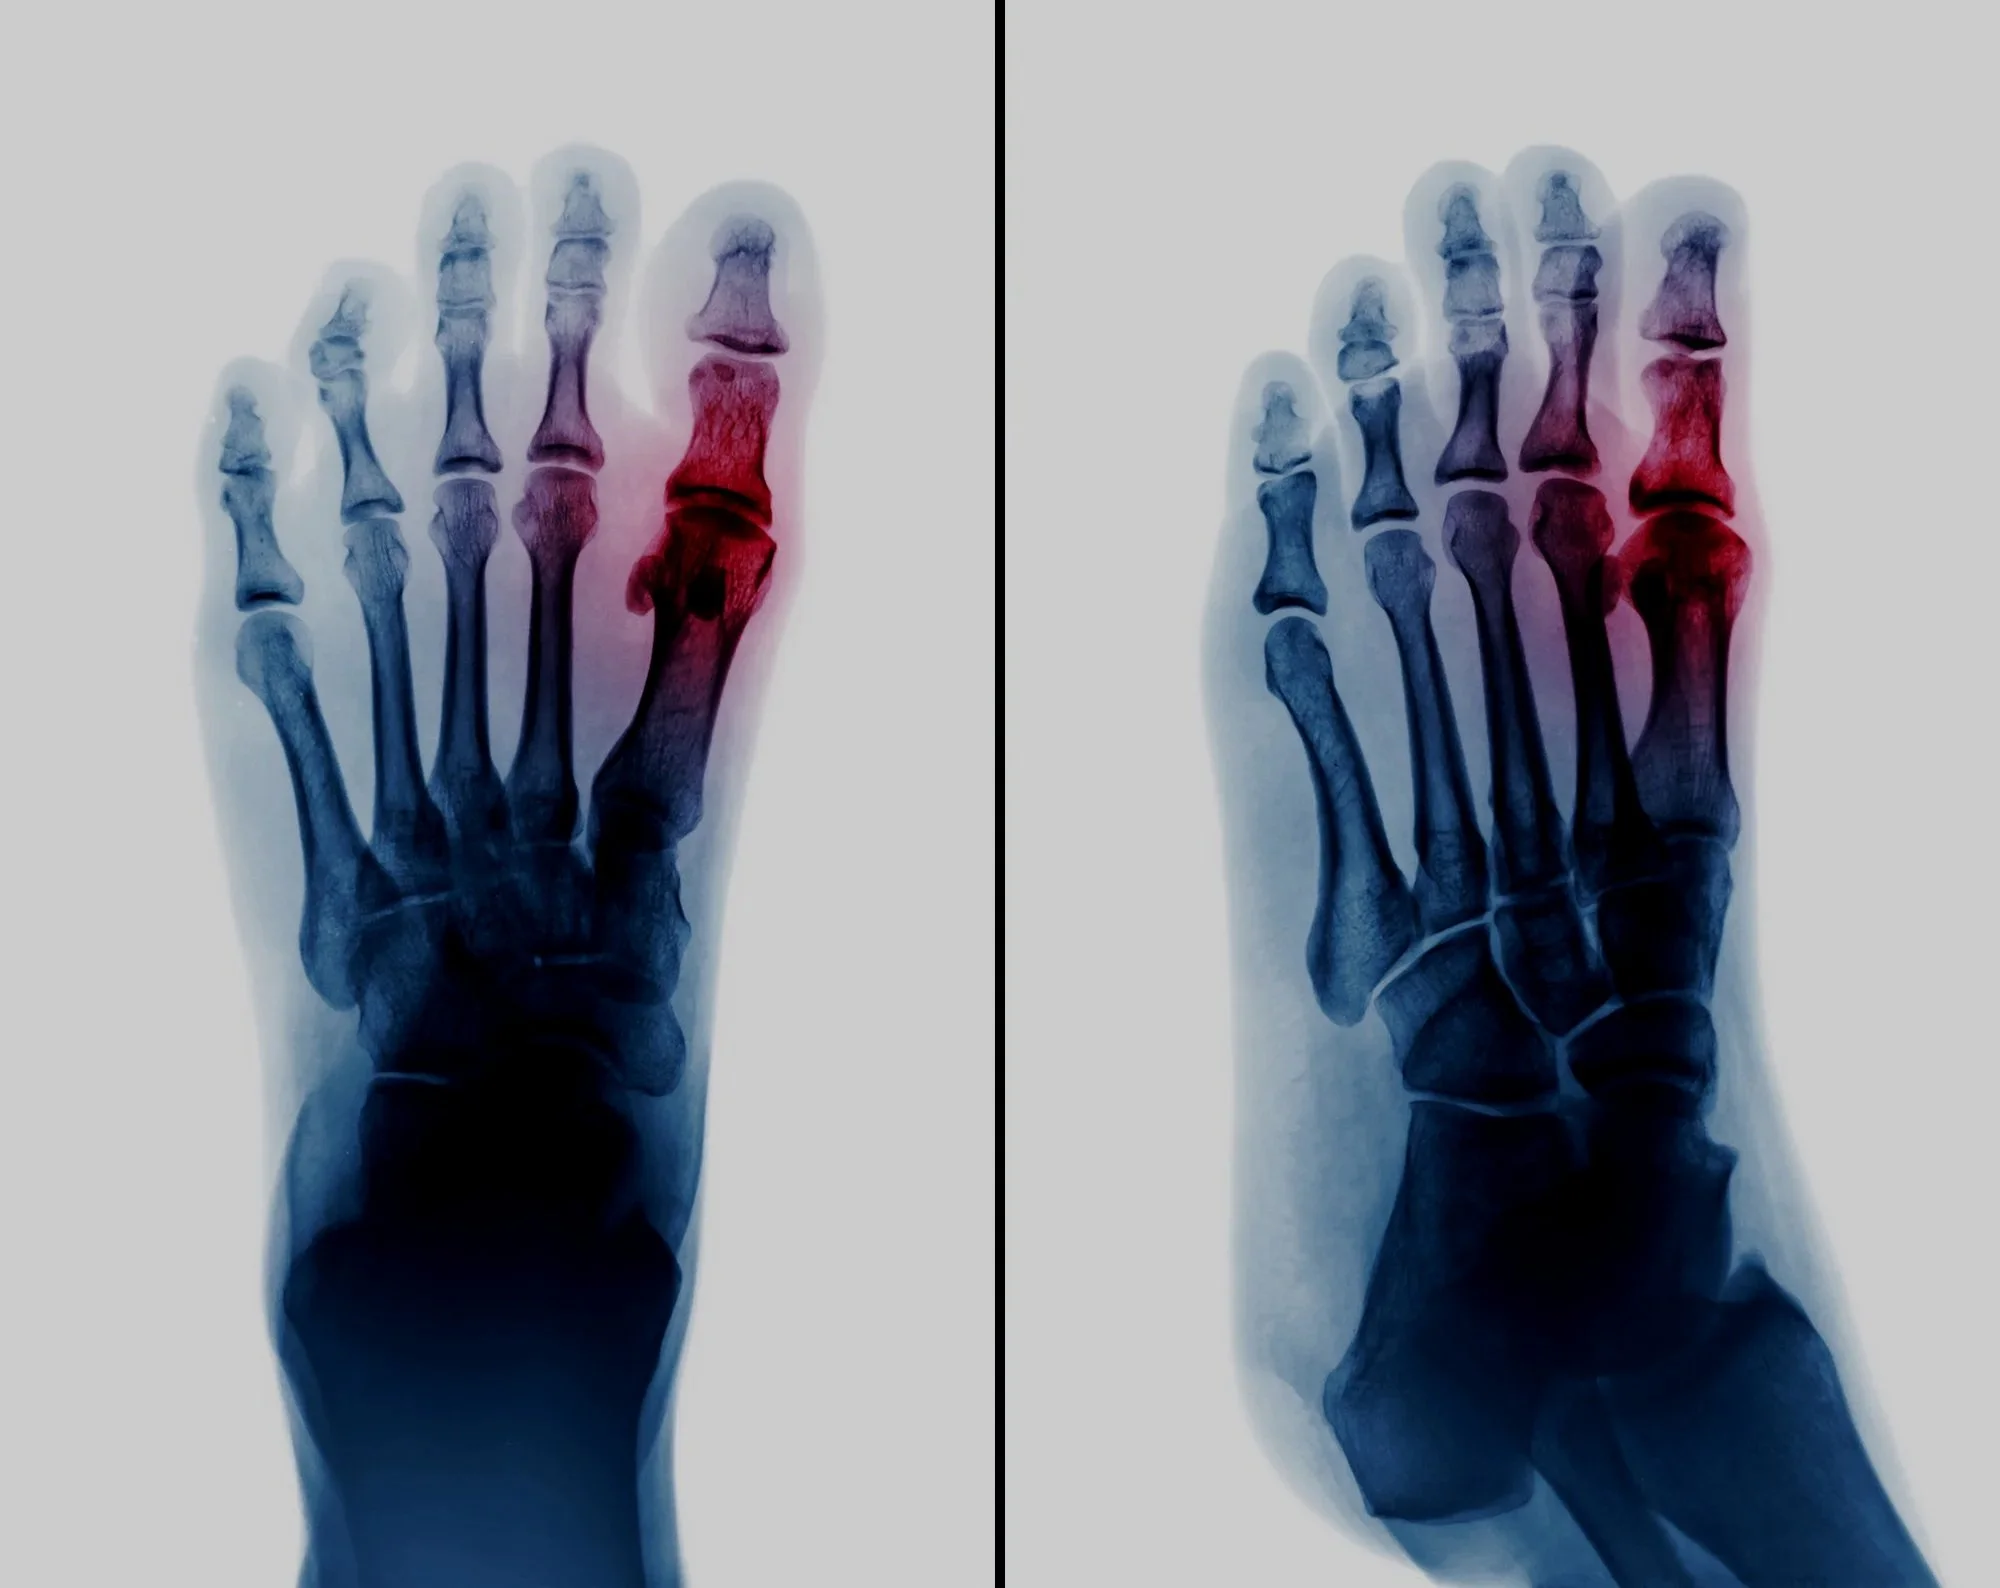

Arthritis of the Big Toe

You have developed arthritis of the big toe joint. This is often associated with a bony bump(s) on the side or top of the joint. This bump may have become red and sore and is often called a 'Bunion'.

Hallux Limitus

Hallux Rigidus

You may have developed bony bumps on the side or top of the foot. To treat Hallux Rigidus the operation, called a joint fusion, will involve removing the joint surfaces from each side of the big toe joint and then holding the bones together while they knit to become one bone. Read more >>